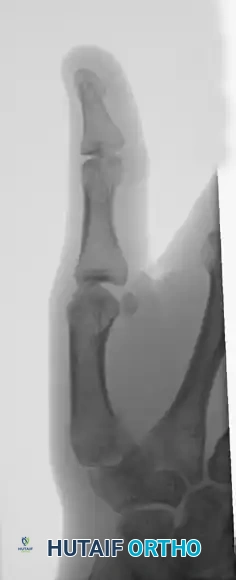

The following sequence illustrates the progression from injury to successful closed reduction and K-wire fixation into the trapezium:

1. Perform closed reduction using longitudinal traction and direct volar-directed pressure over the fracture apex.

2. Secure the reduction with K-wire fixation driven from the metacarpal shaft into the trapezium, bypassing the fracture site to provide a stable strut.